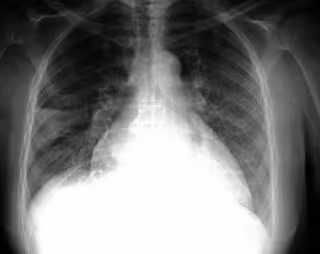

FLICKR/PULMONARY PATHOLOGY/CC BY-SA 2.0